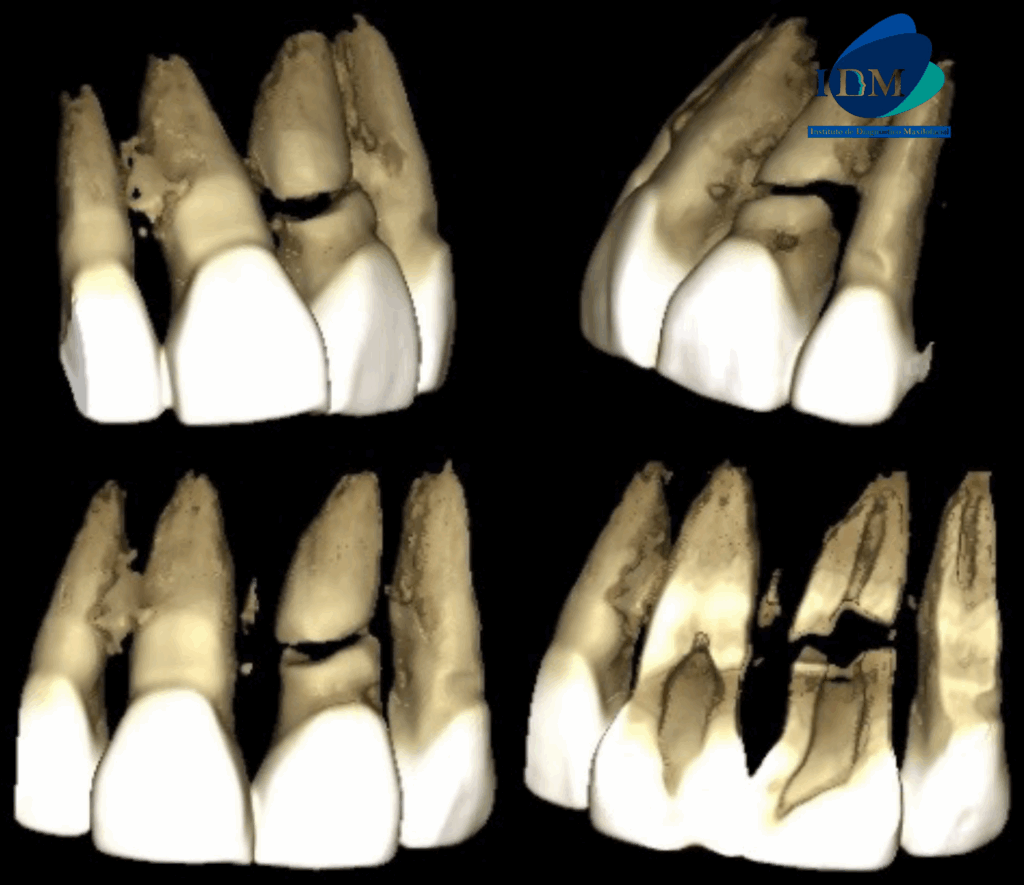

En las reconstrucciones 3D se representa de manera didáctica Fractura Radicular Horizontal (Figura 4).

RECONSTRUCCIÓN 3D

CASO 315 IDM RECONSTRUCCION 3D

• Fractura Radicular Horizontal